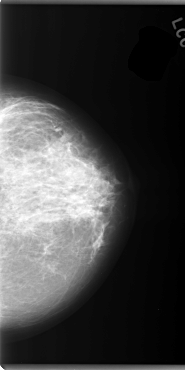

C_0101_1.LEFT_CC

LEFT_CC LINES 5920 PIXELS_PER_LINE 2960 BITS_PER_PIXEL 12 RESOLUTION 50 NON_OVERLAY